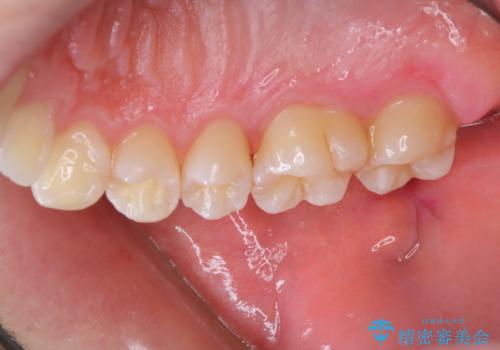

染め出しをして磨き残しのチェックと歯のクリーニング

- 虫歯予防のため、クリーニングと歯磨き指導を希望とのことでした。PMTC30分コース、歯磨き指導を行いました。